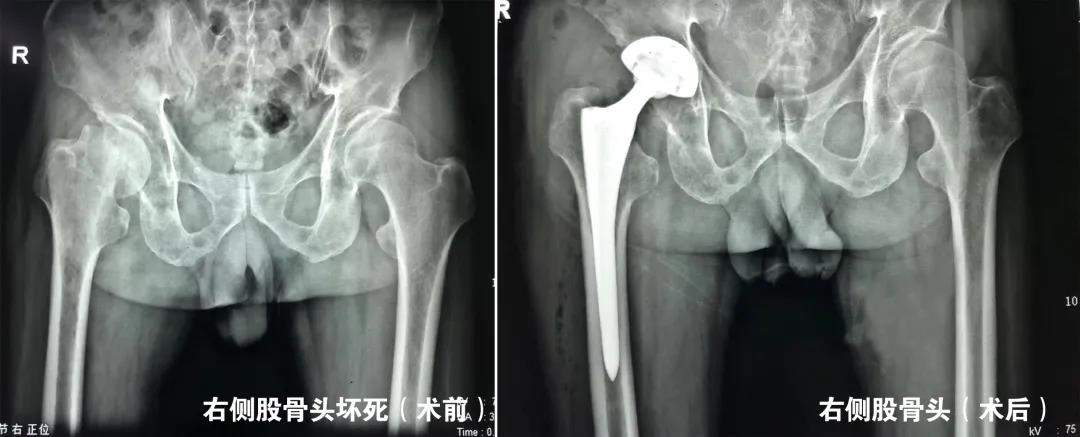

我们根据股骨头坏死的分期不同,根据患者病情“量体裁衣”制定个体化方案,除常规开展微创精准减压治疗股骨头坏死外,对于中末期股骨头坏死即髋关节发育不良导致的继发性股骨头坏死及骨关节炎行全髋关节置换术亦取得了良好的手术效果。